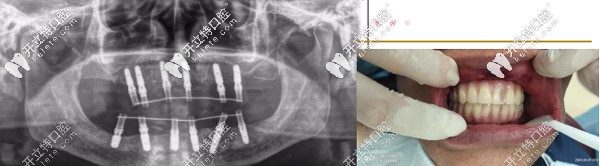

針對魏叔年齡大、口腔條件不佳的復(fù)雜特點(diǎn),熊小明院長為魏叔定制ALL-ON-6即刻種植方案,拔掉剩余松動殘牙,全口種植12顆,修復(fù)24顆牙。

▲魏叔種牙后

手術(shù)當(dāng)天,魏叔叔經(jīng)過消毒、麻醉、拔殘根、種植體埋入、放置基臺及裝牙冠等步驟,手術(shù)僅僅1個小時左右,魏叔缺失的牙齒得以“重生”,看著自己的新牙,高興得合不攏嘴。